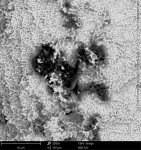

The actual manufacturing, sterilization, and packaging of a dental implant are largely underestimated factors that can affect the short- and long-term condition of the implant. How the implant is made and packaged can influence how surrounding bone interacts with the implant's surface during or after integration. The manufacturing process must be meticulous in all phases to ensure that the end-product is sterile and completely uncontaminated. Although the implant is sterile when removed from the package from the manufacturer, organic and/or non-organic particles on the implant's surface that are directly related to the manufacturing process may be present (Figure 1).11

In particular, organic carbonaceous foreign materials (Figure 2) have been associated with peri-implant bone loss and peri-implantitis.12 Exposure of bone to foreign particles activates macrophages to secrete pro-inflammatory cytokines, such as tumor necrosis factor-α, interleukin (IL)-1b, IL-6, and prostaglandin E2, which, in turn, stimulates the differentiation of osteoclast precursors into mature osteoclasts. The increased osteoclast activity associated with a foreign-body reaction may result in peri-implant bone resorption (Figure 3).13 Foreign materials 0.2 µm to 7.2 µm in size are especially classified as pro-inflammatory.14-16 If such particles detach from the implant surface during the implant insertion process, macrophages take up the particles by phagocytosis and subsequently release pro-inflammatory cytokines, which also leads to the expression of matrix metalloproteinase (MMP-8). The result is an expanding zone of soft-tissue damage and inflammation.13

Quality assessment studies on dental implants conducted by the CleanImplant Foundation in collaboration with Charité University in Berlin and the Sahlgrenska Academy in Gothenburg, Sweden, used scanning electron microscopy (SEM) to identify impurities on sterile-packaged dental implants. Findings of particulate contamination were reported for both titanium and zirconia (ceramic) implants specific to the process used during the manufacture and packaging of those implants.11,17 Reported data demonstrated that one out of three implant systems analyzed contained significant amounts of impurities that are technically avoidable. Those contaminants included organic particles from the manufacturing process, metallic particles of nickel, tungsten, iron, copper, and chromium from the milling or surface treatment process, and plastic from handling and packaging.

SEM images of titanium implants showed not only isolated spots of impurity, but also larger areas of the implant surface that were either insufficiently cleaned in the production process chain or contaminated without being noticed during packaging of the implants. Under high magnification in the SEMs, organic carbonaceous particles appeared as black spots (Figure 4 through Figure 7). The SEM images in low (500x) and high magnification (2,500x) revealed thermoplastic materials, synthetic polymers, and polysiloxanes on sterile implant surfaces. Ceramic implants also demonstrated organic debris related to manufacturing, as some that were analyzed following removal from the manufacturer's packaging exhibited large amounts of predominately organic carbonaceous residue when viewed under SEM (Figure 8 through Figure 11).17